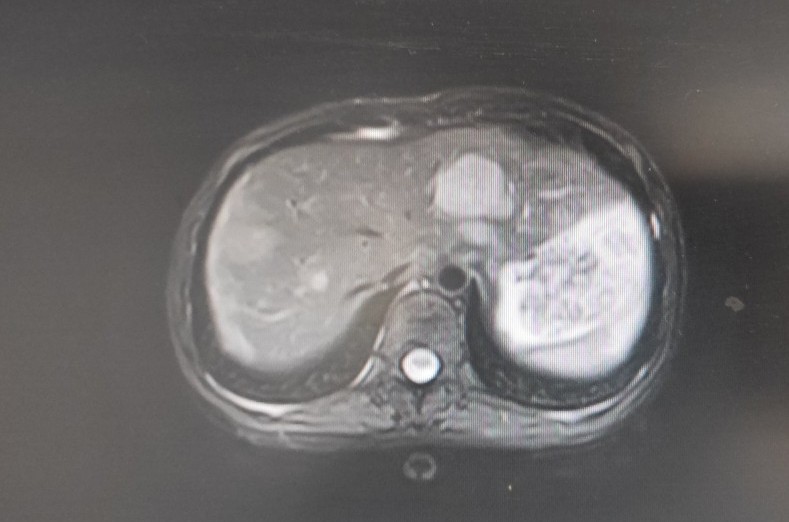

一位22岁的年轻女性,于2020年2月初诉下腹部隐痛,伴腹胀,乏力,就诊门诊妇科,查体发现左下腹一质硬包块,行盆腔核磁共振示:盆腔及子宫腔内多发占位。便收入院治疗,入院做上腹部CT示:肝脏多发低密度占位,考虑转移性病变。